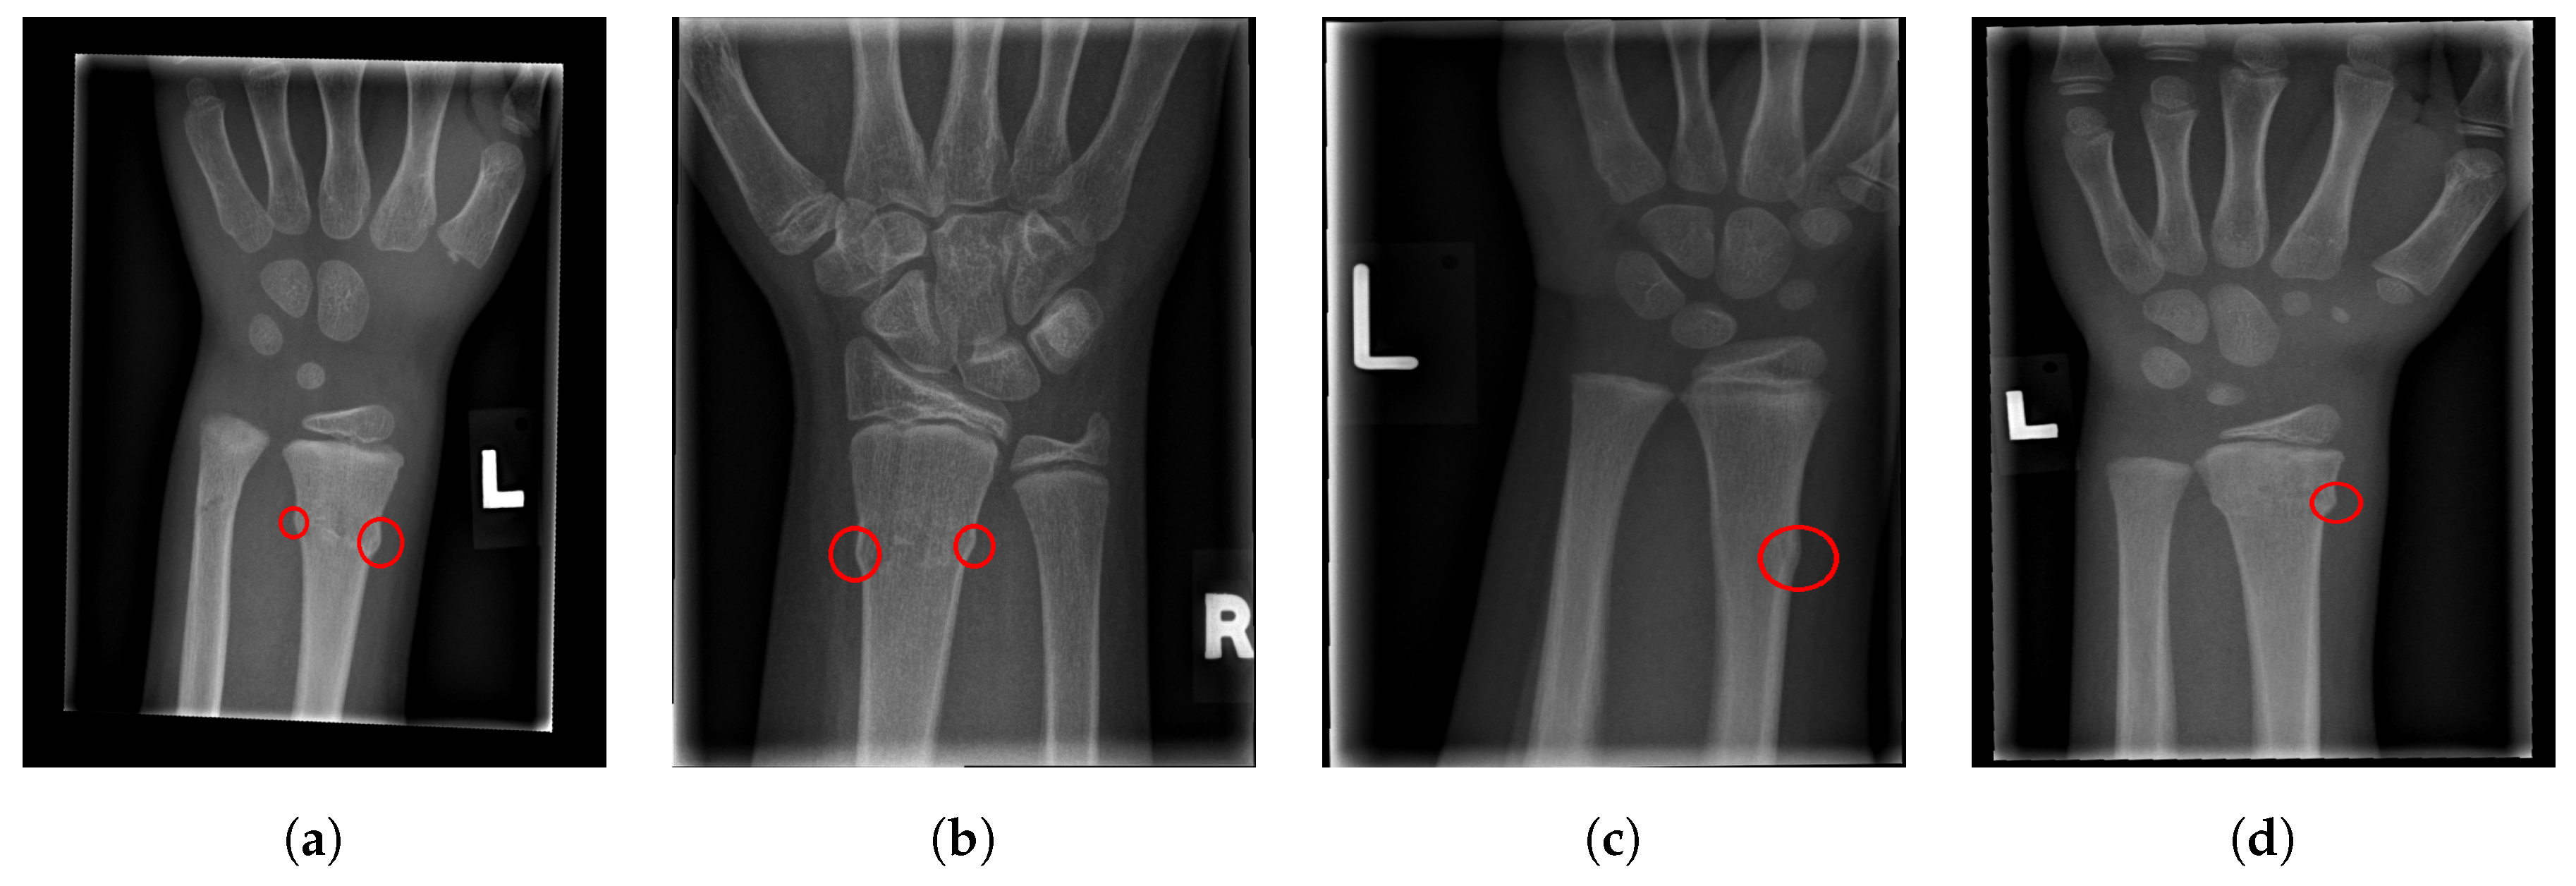

For illustration, four images from each class (TP, TN, FP, and FN) are given in Figure 17, Figure 18, Figure 19 and Figure 20.

Figure 17.

Examples from the true positive (TP) performance metric class.

Figure 19.

Examples from the false positive (FP) performance metric class.

Figure 20.